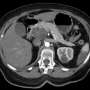

The drug, which targets specific genetic mutations present in many pancreatic tumors, has shown a significant reduction in tumor size among trial participants. Doctors report that some patients are experiencing a remarkable response, with symptoms alleviating and quality of life improving during treatment.